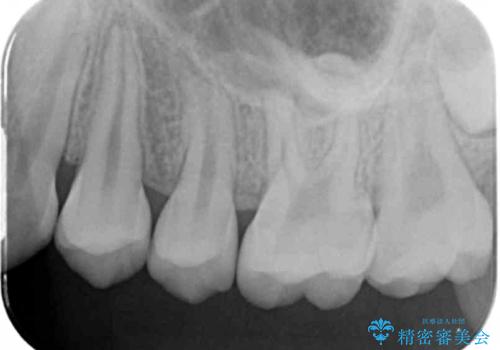

他院で治療した部分の気泡 セラミックインレーでの修復

特に症状はありませんでしたが、レントゲン上で気泡が確認されたため再治療を行っていきます。

気泡が入ってしまっている部位は歯ブラシでのお掃除が難しく、放置してしまうと虫歯が広がってしまうリスクもあるため精度の良い詰め物で修復処置を行います。